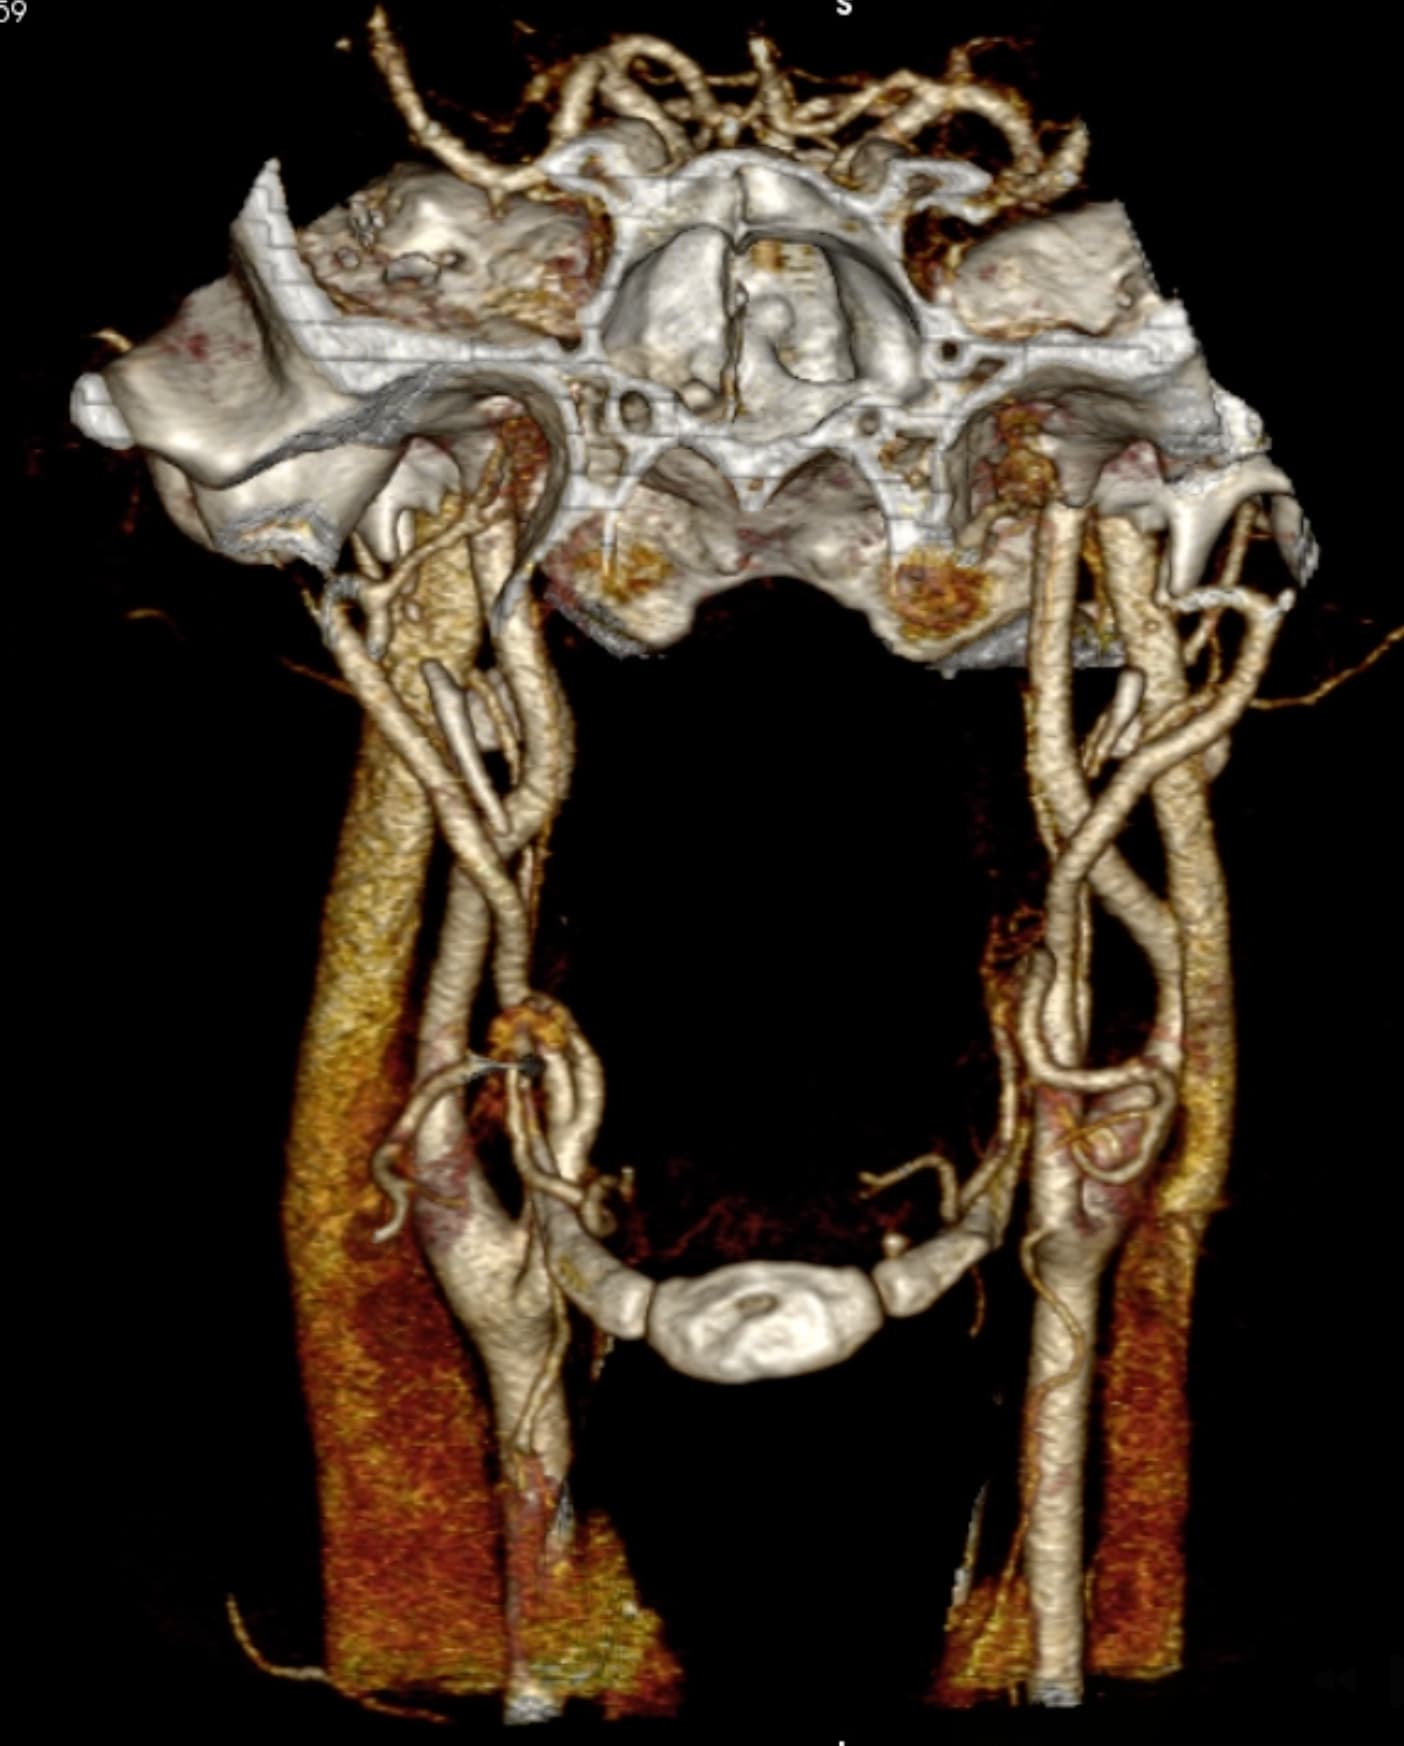

So, 2 years ago was the first time I came across Living with Eagle, filled with descriptions of all my symptoms, and a slew of scans showing very obvious bone chunks in the neck. Since I studied bio in college, and these bones are obvious, I figured I’d take a stab at looking at my own past scans and, low and behold, mild–but present–ossification of my stylohyoid ligament. Perhaps more relevant in my case, in the process of learning enough of the anatomy to understand axial images I noticed another weird thing–my right external carotid artery is in the wrong place. Instead of sitting lateral to my hyoid greater cornu, it’s medial. Hmm.

Tonsil surgery did solve the problem of my tonsils hurting, because they were gone, but no resolution of other symptoms. This was a year ago. I’ve been to PT, SLP, and now back to PT while I trial gabapentin for the neurologist. PT#2 discovered a bunch of significant atrophy in my upper right shoulder/back, and, you guessed it it’s all right sided. I’ve since then, thanks to radiopedia and Netter’s, also explored my images and noticed a few other anomalies in my scans, including an extended right thyroid superior cornu which appears to be pressing strongly into my neck also in the general area of pain, and an occipital artery branching off and wrapping around the internal carotid. Frustratingly these also weren’t mentioned on rads reports. My swallow study by the SLP showed obvious asymmetry with my swallow, but the SLP reported it symmetric and radiology apparently doesnt read the A/P view in their modified barium swallow studies? This is not inspiring faith in the academic institution I attended, but what can I possibly know they dont?

I’m here cause I’ve learned so much, and ya’ll seem to be the internet experts of weird head/neck issues adjacent to the stylohyoid chain. The docs keep seeing me, and keep ordering imaging, and seem to not be talking to each other at all? Frankly it seems to me the answers are in already in the images… so I’ve included several, perhaps you’ll see something helpful and can offer a suggestion… I just know I’m exhausted, frustrated, in so much pain all the time I cannot function which is so demoralizing, and it’s getting worse despite physician recommendations.

I wish I had better words for my existing doctors, or a doctor to visit familiar with these symptoms, if they’re sufficiently connected. Here are some scans for those interested, maybe someone has some ideas I can share with one of my doctors. I’m definitely at a loss and the pain constant and debilitating.